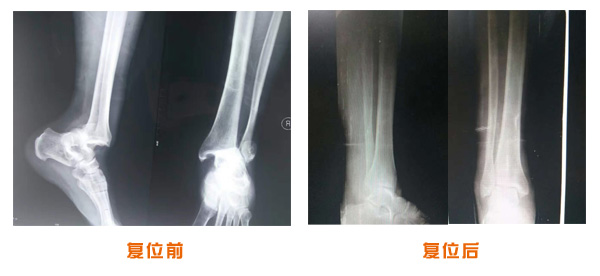

踝關(guān)節(jié)脫位骨折治療前后對比